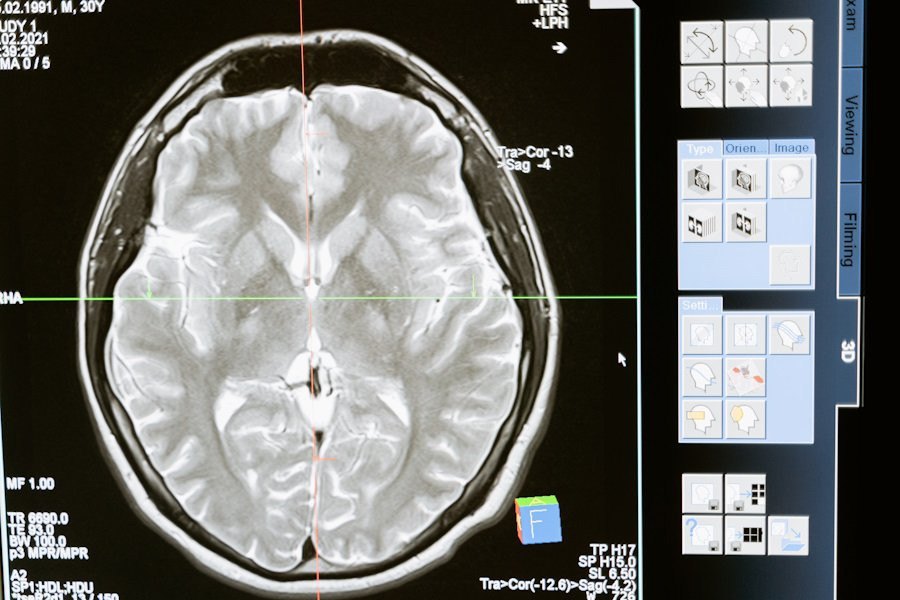

Ученые из Pennsylvania State University опровергли устоявшееся мнение о том, что каждое полушарие мозга контролирует противоположную часть тела. Результаты их исследования, опубликованные на портале Journal of Physiology, могут изменить подходы к реабилитации пациентов после инсульта.

Новая модель, называемая гипотезой комплементарного доминирования, показывает, что оба полушария мозга вносят свой вклад в управление движениями. Доминирующее полушарие отвечает за плавные и эффективные движения, тогда как недоминантное полушарие контролирует устойчивость и сопротивление неожиданным условиям.

Эти открытия предполагают, что повреждения одного полушария мозга могут вызвать специфические нарушения не только в противоположной руке, но и в руке на той же стороне повреждения. Новое вмешательство, разработанное учеными, помогает уменьшить эти дефициты и улучшить функциональную независимость у пациентов после инсульта.